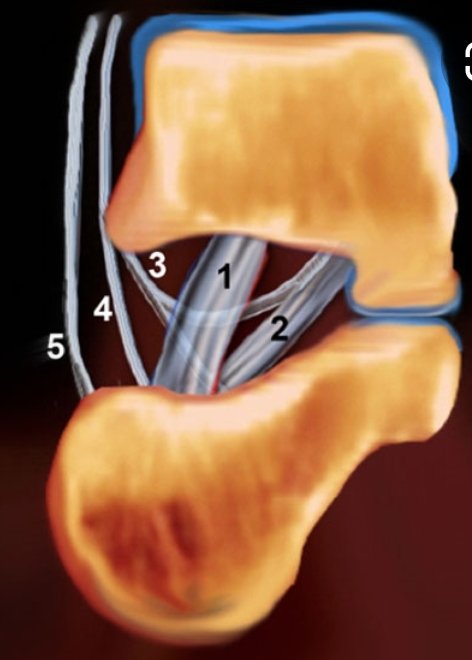

Anatomy ilustration from

#radiologyassistant. Number 3 is the medial root/fascicle of the inferior extensor retinaculum.pic.twitter.com/eAEmJHqvhb